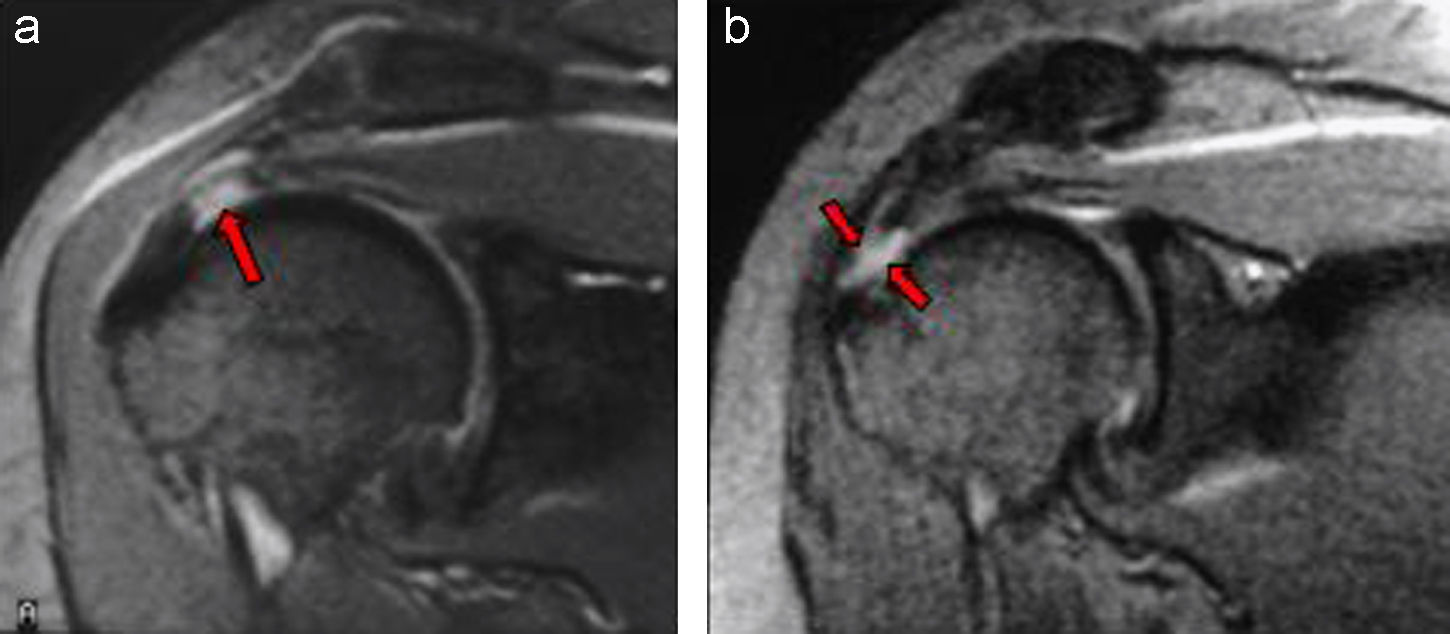

En este estudio poblacional, las anomalías del MR fueron casi universales después de los 40 años y mostraron poca concordancia con los síntomas del hombro. Estos hallazgos sugieren que las anomalías del MR a menudo representan cambios normales relacionados con la edad, en lugar de enfermedad, y cuestionan el valor clínico de las pruebas de imagen de rutina para el dolor de hombro atraumático. JAMA Internal Medicine, febrero de 2026.